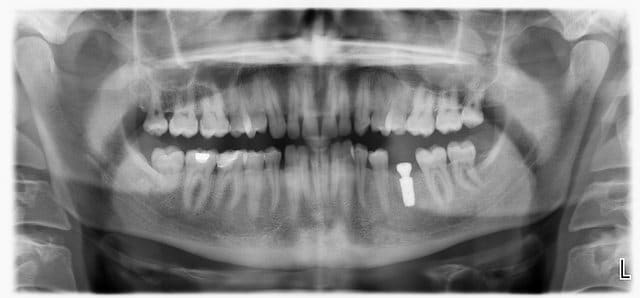

Voilà une image similaire dans le sinus gauche.

J'avais adressé à l'ORL qui avait fait faire un scanner des sinus et diagnostiqué un polype.

Ceci étant totalement asymptomatique, il a décidé de ne rien faire.

Je revois mon patient régulièrement pour contrôler l'implant et à chaque fois la lésion ne montre aucune évolution.